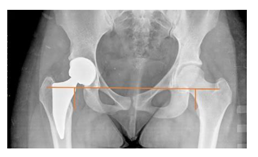

| Leg length discrepancy | Trochanteric method: the difference between the distances from the tip of the lesser trochanter to the interteardrop line, measured in both the hips [29] +/−: the treated hip was longer/shorter | 0 ± 10 mm | ![]() |